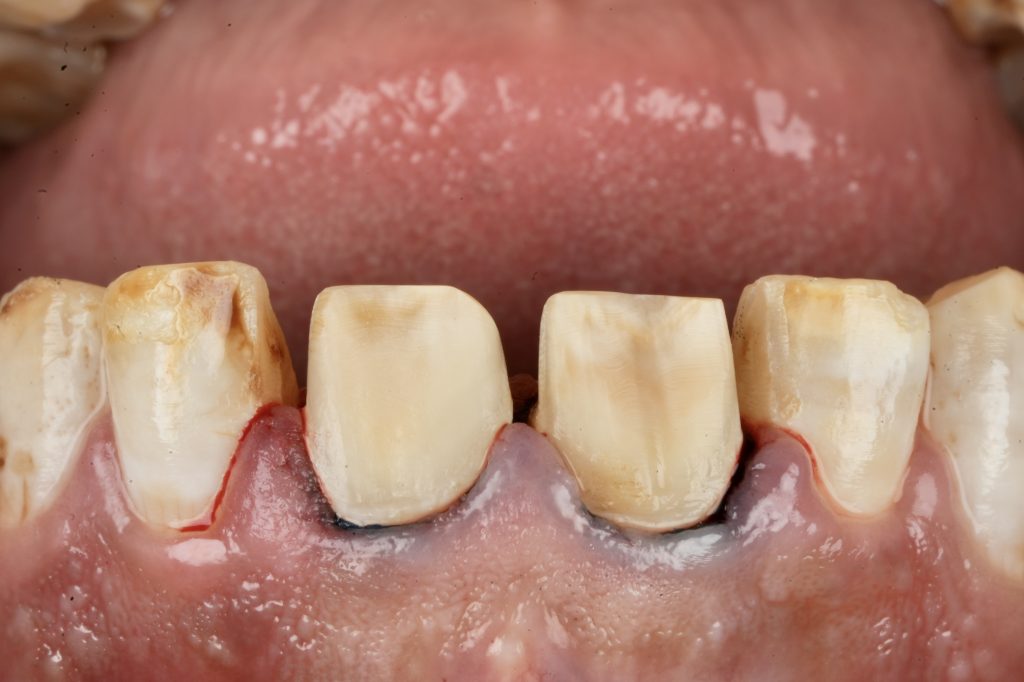

5️⃣ Adhesive Protocol and Bonding

Each veneer was etched with 9 % HF acid for 20 seconds, silanated, and dried. Teeth were treated with 37 % phosphoric acid and universal adhesive (Clearfil Universal Bond Quick). Light-cure resin cement (Variolink Esthetic LC) was applied under full-arch rubber-dam isolation. Excess cement was removed and polymerization performed for 40 s per surface (Fig 4).